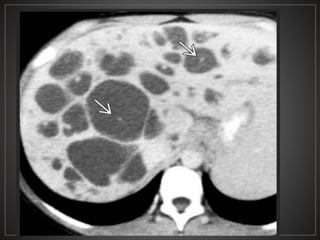

• #53 El CT axial con contraste muestra una dilatación masiva de los conductos biliares intrahepáticos. punto "central" o "excéntrico" en muchas de las estructuras quísticas, que representan las venas portas, un clásico hallazgo de imágenes en la enfermedad de Caroli.

• #54 CT contrastada fase portal, observan imágenes hipointensas con un centro hiperintenso en relación a dilatación sacular árbol biliar (central dot)